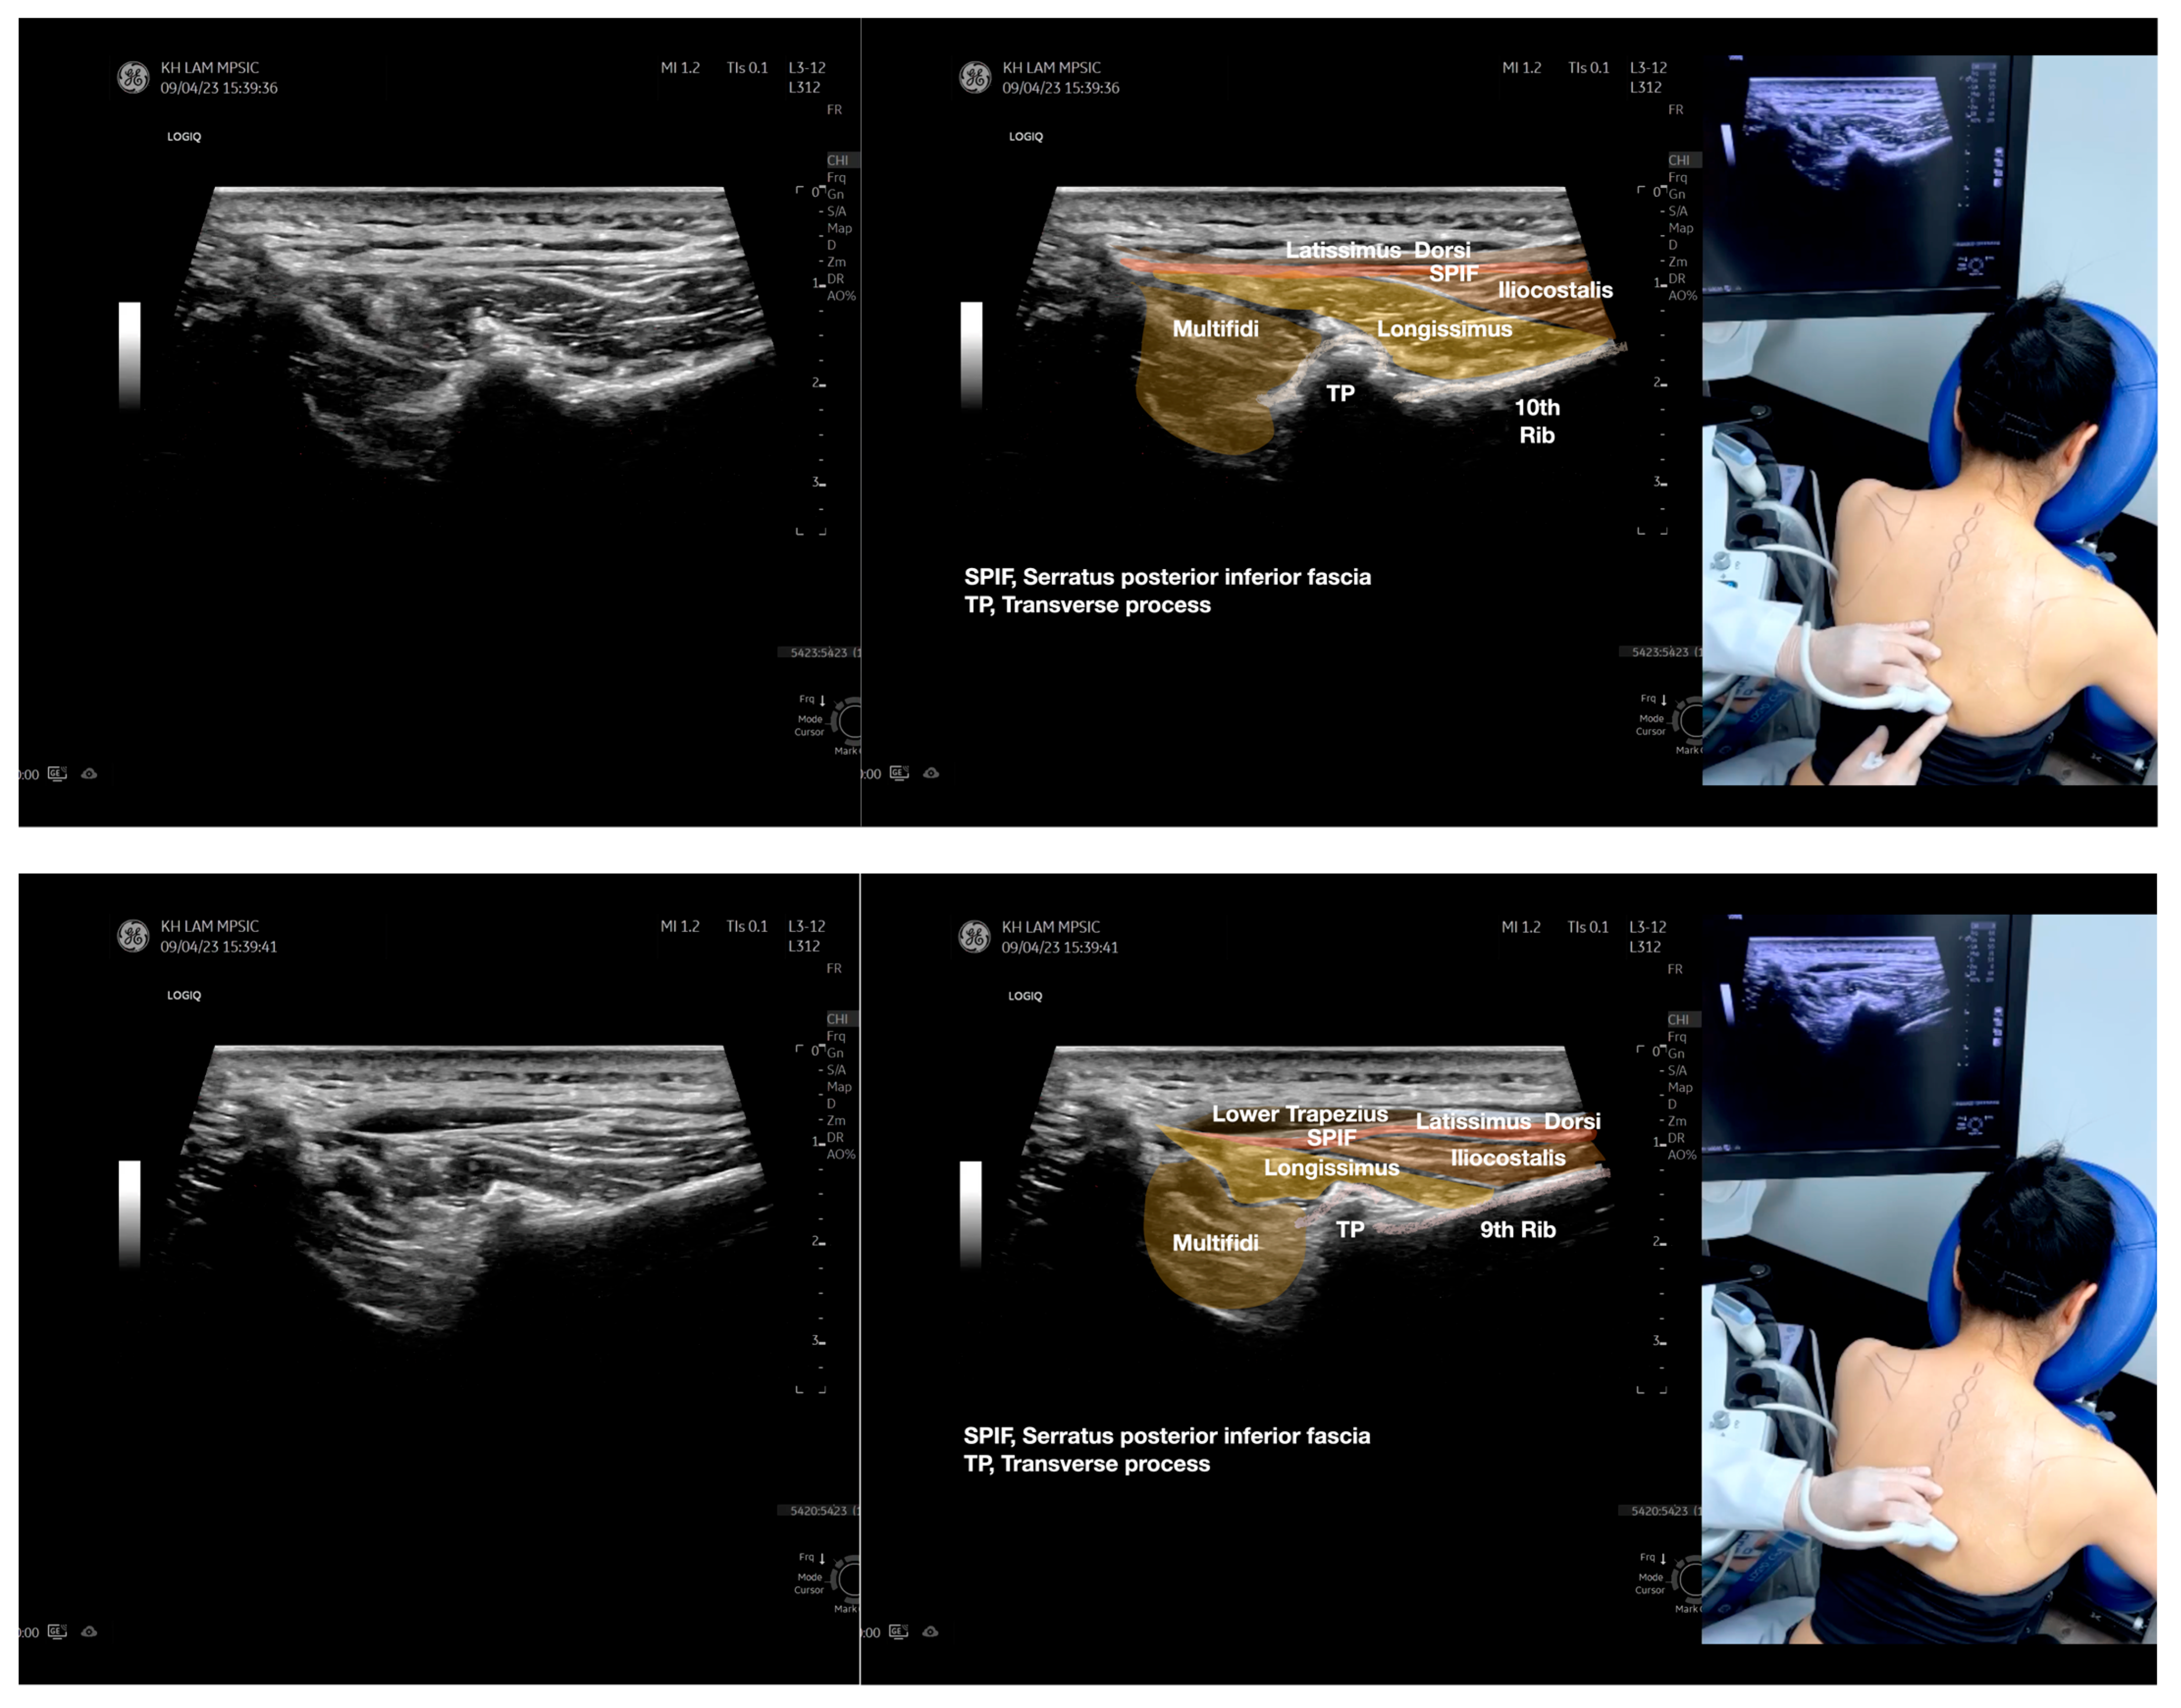

Figure 2.

Sonoanatomy of the lateral border of the inferior trapezius, its related muscles, and the infraspinatus fascia. The step-by-step scanning techniques of the structures illustrated in this figure have been shown in Video S6. Available online: https://www.dropbox.com/s/vjj49wiwdsidouz/Figure%202.docx?dl=0 (accessed on 1 January 2023). Dynamic ultrasound scanning of the anterior shoulder with the humerus externally rotated (palm up), elbow straight, and the shoulder actively flexed and abducted at about 90 to 100 degrees shows that the fibrotic and thickened bursa was noted to be snapping between the subscapularis tendon and the coracoacromial ligament, as shown in Video S3. The patient noticed this snapping during many of his daily activities with his shoulder flexed just above 90 degrees, e.g., taking off clothes and combing hair. Ultrasound-guided injection of the thickened and fibrotic bursa did not reproduce the usual pain nor reduce the pain, and it did not improve the shoulder snapping and flexion power with the elbow straight, shoulder flexed to 90°, and the humerus externally rotated (palm up). Ultrasound-guided injection of the cortical break reproduced the concordant pain and temporarily and partially reduced the pain with snapping and residual anterior shoulder pain (Video S4), but it did not change the snapping or weakness in the right shoulder flexion with the humerus in external rotation. With the failure of direct anterior treatment to the suspected lesions, it was essential to further explore other causes for the anterior painful snapping. Further detailed musculoskeletal examination of the scapular movement showed that the right scapulothoracic movements were not smooth compared to the left counterpart (Video S5) [4,5]. There might be some disruptions in the right infraspinatus fascia (IF) and its related muscles, including the lateral edge of the right inferior trapezius, rhomboid minor and major [6], teres major, latissimus dorsi [7,8] (LD), and posterior deltoid attachments to the IF [9,10]. Clinically, prominent and active trigger points were observed in the right infraspinatus muscle. Holding the inferior angle of the scapula, with the examiner’s fingers, especially over the origin of the teres major muscle over the scapula, the latissimus dorsi [11,12,13] and the scapular insertion of the rhomboid major muscle significantly improved the power of the resisted shoulder flexion with the elbow straight and the shoulder flexed to 90° with the humerus externally rotated (palm up). In order to illustrate the utilization of ultrasound-guided sonopalpation and ultrasound-guided digital palpation for detecting the suspected lesions of the IF and its related muscles, we presented the following videos (Videos S6–S9) and still images (Figure 2, Figure 3, Figure 4 and Figure 5) to demonstrate the essential techniques and crucial points of getting the normal sonoanatomy of the IF and its related structures. The gross anatomy of the IF and its related muscles were also shown in Figure 6, Figure 7 and Figure 8.